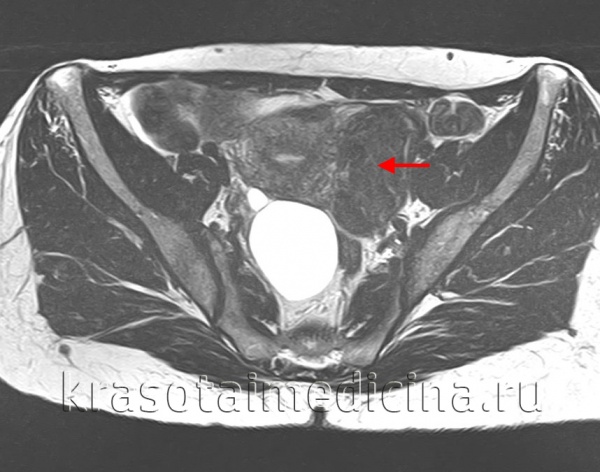

Для диагностики миомы матки чаще всего достаточно ультразвукового исследования. Обычный гинекологический осмотр на кресле – неинформативный метод диагностики миомы. С его помощью невозможно выявить, например, небольшие миоматозные узлы, которые не увеличивают общие размеры матки. МРТ малого таза применяют только при очень больших размерах матки и узлов. Проведение гистероскопии (исследование полости матки миниатюрной камерой) целесообразно при субмукозных узлах (растущих в полость матки).

Для уточнения диагностических сведений возможно проведение гистеросальпингографии, гистероскопии (при субмукозных миомах), МРТ органов малого таза. При необходимости исключения малигнизации множественной миомы матки производится РДВ с гистологическим исследованием соскоба либо аспирационная биопсия с цитологией аспирата. Диагностическая лапароскопия показана, главным образом, для дифференциальной диагностики субсерозных миом с солидными опухолями яичников, и забрюшинными новообразованиями.

Если размер матки настолько велик, что возможности УЗИ не позволяют полностью оценить ее — рекомендуется проведение МРТ малого таза. Этот метод подробно отображает всю картину заболевания и позволяет оценить размер и точную локализацию узлов.